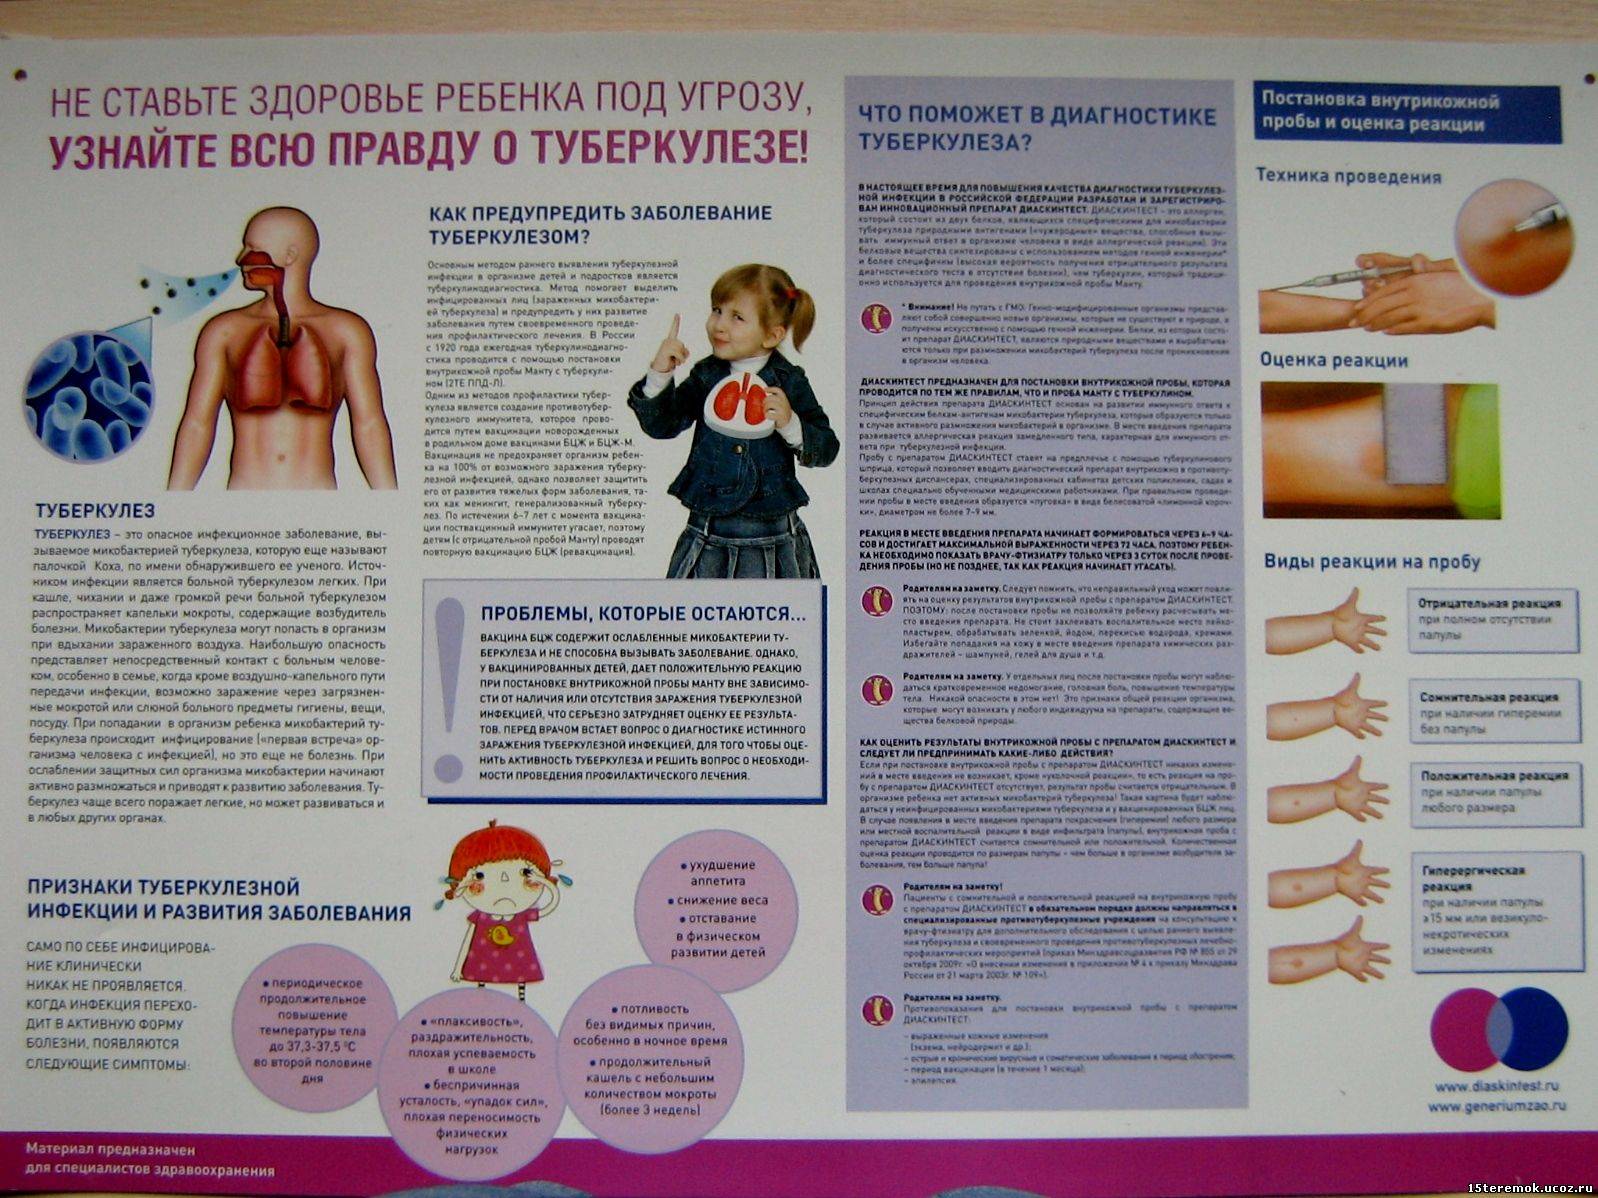

Симптомы туберкулеза: Как распознать и что делать

Раздел: Визуальные уроки